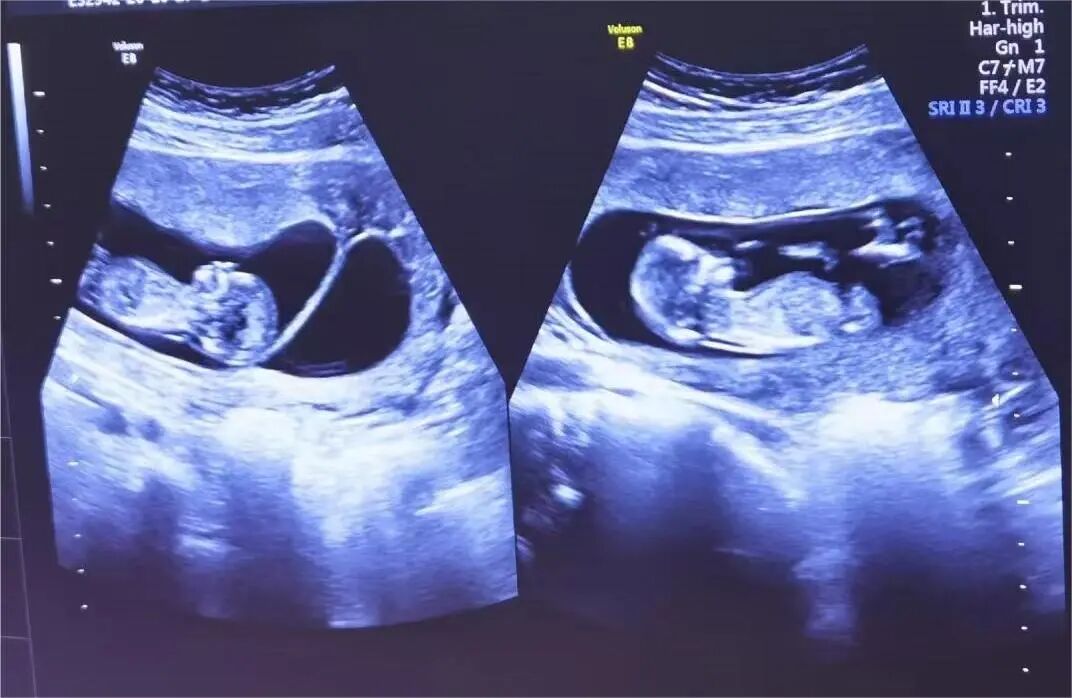

1月7日,贵州航天医院第91次晨读会由我院超声科医师杨向蓉作学术交流,她以“小微泡,大作用——右心声学造影”为题,详细讲解了右心声学造影的基本原理、适用情况、操作方式及心脏异常分流评估特点等内容,涵盖了该技术的实施条件、所用造影剂类型及多种激发试验方法,并通过多个病例图文资料分享了右心声学造影在相关症状病因探寻中的辅助角色,为临床评估提供了一种观察途径,有助于从循环角度了解某些症状的可能原因,在相应症状的病因分析中具有一定的参考意义。 贵州航天医院 超声科专家简介 吴艳辉 中共党员,超声科学科带头人,主任医师 专业擅长:从事超声诊断工作30余年,对心血管、小器官超声、超声引导下介入等具有丰富的临床经验。 胡大海 超声科主任,副主任医师 专业擅长:从事超声工作20余年,对心血管、外周血管、浅表器官、成人颅脑、超声造影诊断及超声引导下介入等具有丰富的临床经验。 骆科美 中共党员,超声科副主任医师 专业擅长:从事超声诊断工作30余年,对胎儿心脏及颅脑、妇产超声诊断、盆底超声等具有丰富的临床经验。 刘 敏 超声科副主任医师 专业擅长:从事超声诊断工作20余年,对妇产科超声、心脏血管超声诊断具有丰富的临床经验。 韩锡铁 超声科副主任医师 专业擅长:从事超声诊断近20年,对心血管、外周血管、浅表器官、肌骨神经超声诊断具有丰富的临床经验。 杨向蓉 中共党员,超声科主治医师 专业擅长:从事超声诊断工作16年,擅长心血管、浅表器官、盆底、腹直肌超声、右心声学造影及超声引导介入等技术。 贵州航天医院超声科简介 基本情况 贵州航天医院超声科配备多种超声检查设备(飞利浦彩超(IU-22、IU-Elite、EPIQ5、EPIQ7),迈瑞彩色超声(ResonaI9T、RechoR9、Resona I9、DC-8)、GE-VolusonE8、汕头SIUIAPogee6800、床旁彩色超声诊断仪等),设有心血管诊室、外周血管诊室、妇产科诊室、腹部诊室、绿色通道、浅表小器官等检查室。 诊疗范围 科室业务覆盖腹部、泌尿、妇科、产科(常规、NT筛查、系统筛查及高危妊娠监护)、成人心脏、外周血管、浅表器官(包含甲状腺、乳腺、阴囊、眼睛等)、颅脑(小儿颅脑、成人帕金森辅助筛查)、小儿肺超、超声造影、盆底、腹直肌、肌骨神经等检查及各种超声介入引导。 专科特色 四肢血管超声检查、产前系统筛查及超声监护、超声造影检查技术、介入超声临床应用、经颅脑实质超声辅助筛查诊断帕金森病、小儿髋关节筛查、女性性早熟超声诊断、盆底、腹直肌超声检查等。 NT超声检查 超声介入引导 肝脏超声造影 甲状腺造影 颅脑超声帕金森辅助检查 乳腺超声造影 上肢动静脉造瘘超声检查 双胎超声筛查 下肢血管超声检查 右心造影 end